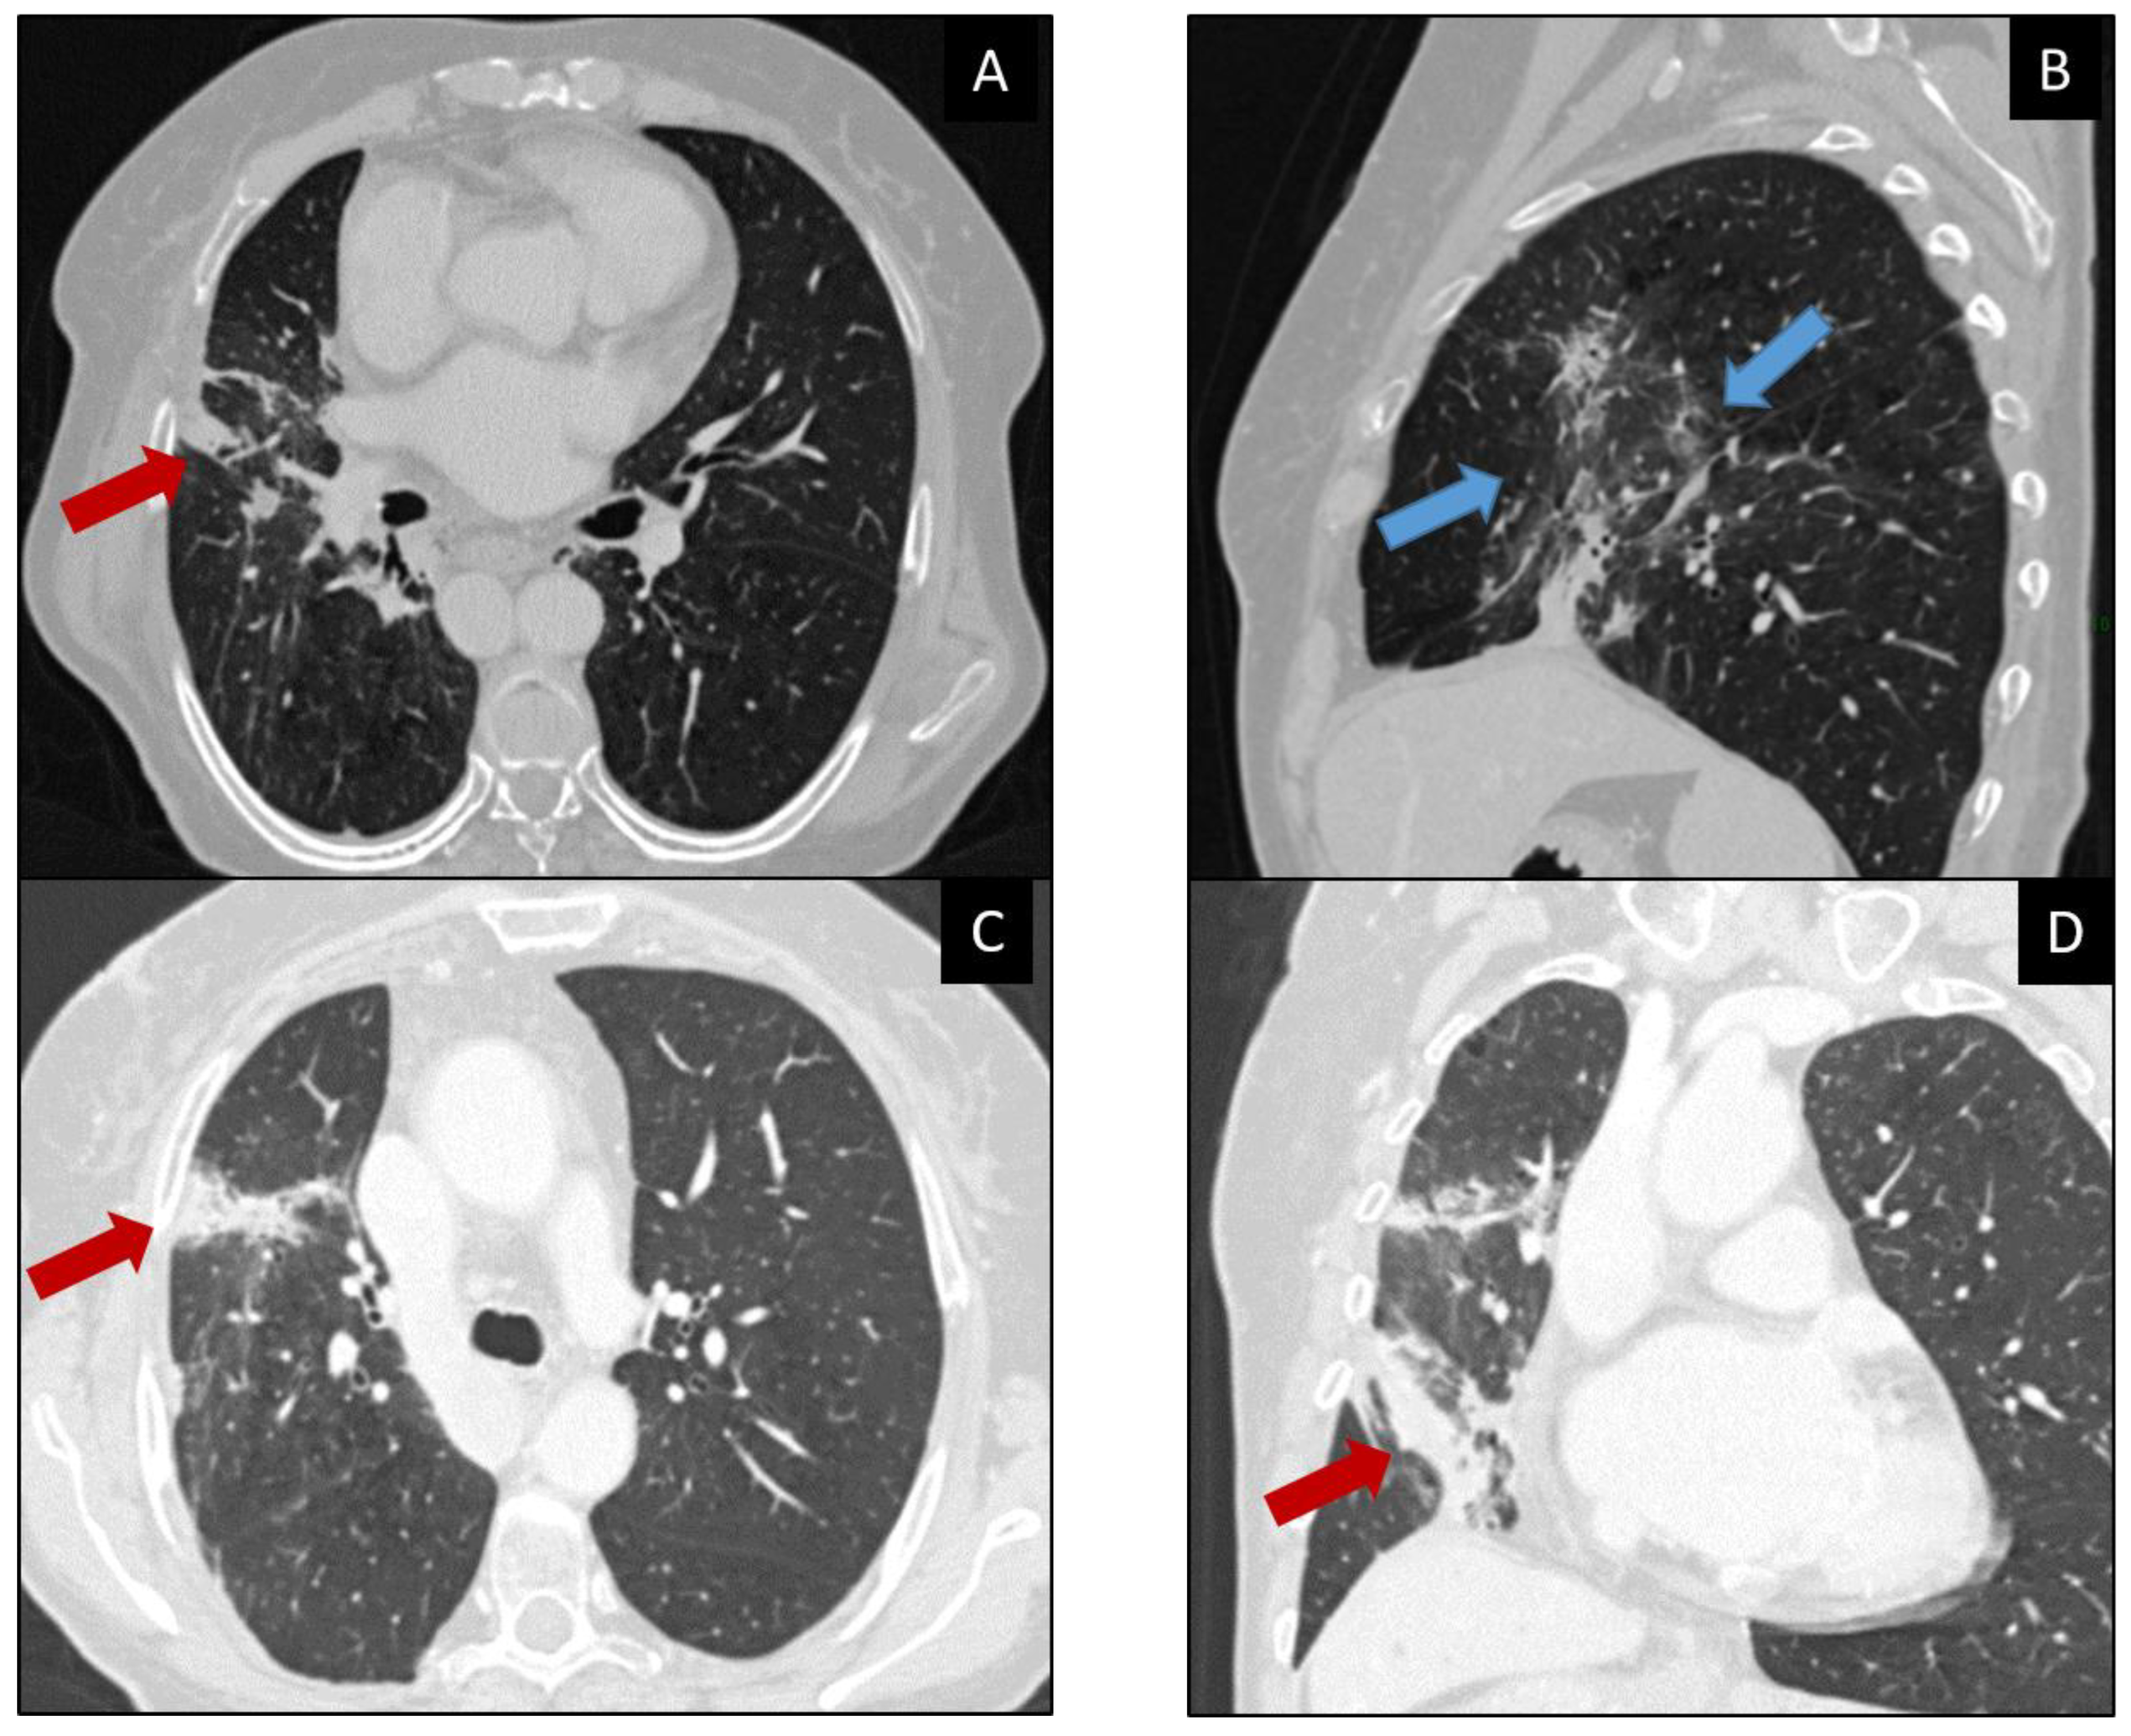

5.3. Diagnosis and Imaging and Differential Diagnosis

- Kalisz, K.R.; Ramaiya, N.H.; Laukamp, K.R.; Gupta, A. Immune Checkpoint Inhibitor Therapy-related Pneumonitis: Patterns and Management. Radiographics 2019, 39, 1923–1937. [Google Scholar] [CrossRef]

- Nishino, M.; Ramaiya, N.H.; Awad, M.M.; Sholl, L.M.; Maattala, J.A.; Taibi, M.; Hatabu, H.; Ott, P.A.; Armand, P.F.; Hodi, F.S. PD-1 Inhibitor-Related Pneumonitis in Advanced Cancer Patients: Radiographic Patterns and Clinical Course. Clin. Cancer Res. 2016, 22, 6051–6060. [Google Scholar] [CrossRef]

| CT Patterns of Pneumonitis (in Order of Incidence) | CT Findings | Location | Differential Diagnosis |

| COP |

|

| NSIP |

| |

| HP |

| AIP/ARDSuncommon and severe |

| Sarcoid-like reaction |